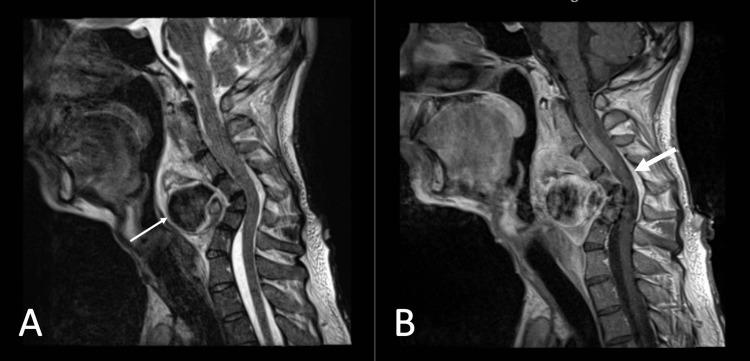

Neurofibromatosis type 1 (NF1) is a variable penetrance autosomal dominant condition predominantly involving the peripheral nervous system. NF1 exhibits a wide spectrum of clinical patterns involving the skin, eye, brain, spinal cord, and, to a lesser extent, long bones and arteries. Arterial stenosis or aneurysms have been variously studied, but the association with NF1 has not been firmly established. A 31-year-old gentleman with NF1 experienced progressive neck pain over a five-month period, associated with limited range of motion and dysphagia. Magnetic resonance imaging (MRI) of the cervical spine suggests paraspinal plexiform neurofibromas with excessive reverse cervical lordosis. Further workups revealed a large left vertebral artery fusiform aneurysm and a pseudoaneurysm. The patient made a full recovery following endovascular embolization. It is crucial to maintain a high index of suspicion for vascular malformations in patients with NF1. The pathogenesis of vascular manifestations in NF1 and options for therapeutic management were discussed.

1型神经纤维瘤病(NF1)是一种外显率可变的常染色体显性疾病,主要累及周围神经系统。NF1表现出广泛的临床模式,涉及皮肤、眼睛、大脑、脊髓,在较小程度上还涉及长骨和动脉。动脉狭窄或动脉瘤已得到各种研究,但与NF1的关联尚未得到确凿证实。一名31岁患有NF1的男性在五个月的时间里经历了渐进性颈部疼痛,伴有活动范围受限和吞咽困难。颈椎磁共振成像(MRI)显示椎旁丛状神经纤维瘤伴颈椎过度反曲。进一步检查发现一个巨大的左侧椎动脉梭形动脉瘤和一个假性动脉瘤。患者在血管内栓塞术后完全康复。对NF1患者的血管畸形保持高度怀疑指数至关重要。讨论了NF1血管表现的发病机制和治疗管理选择。